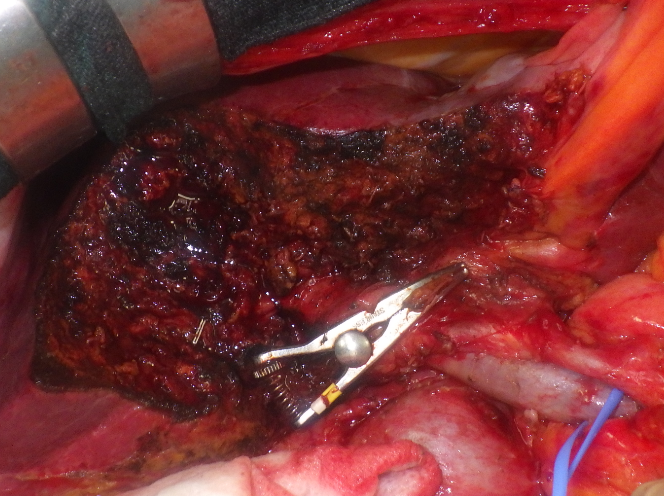

術中画像